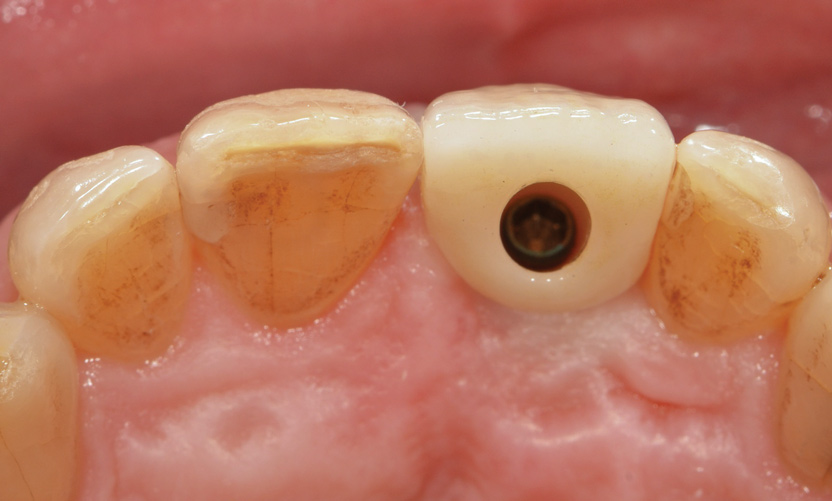

Fig 9. Palatal view (laboratory) of implant-retained crown with access opening ideally positioned in cingulum due to use of the angulated screw channel system.

Figure 9